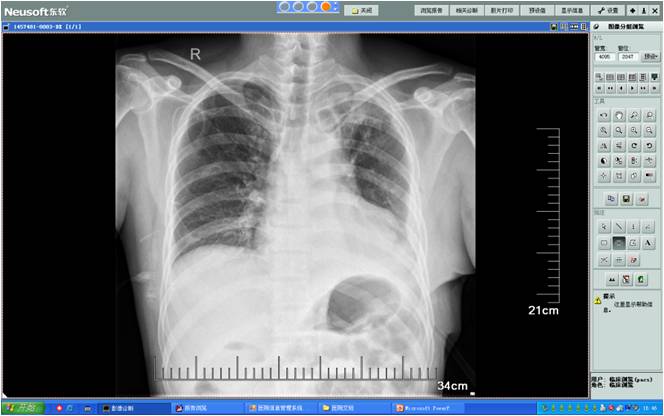

术后DR胸片